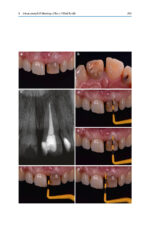

Tooth Whitening: An Evidence-Based Perspective 2023

کتاب افست “Tooth Whitening: An Evidence-Based Perspective 2023” ویرایش دوم